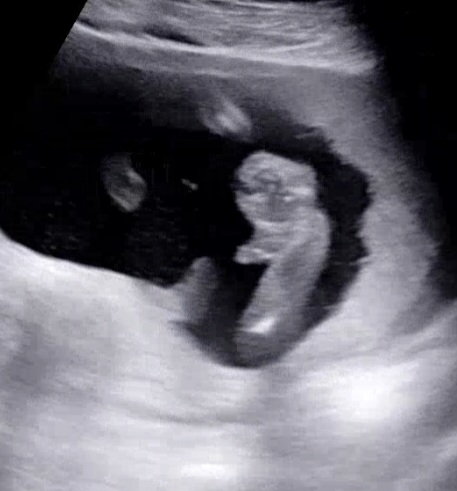

16주5일 성별 반전 역시나 없네요🥰

원장님이 오우 이러시는데 빵 터졌어요 ㅋㅋ 그 차분하고 진중하신분이 그런 반응이라니 ㅋㅋㅋㅋㅋㅋㅋㅋㅋ 오늘 성별 확정 받았는데 완전🌶 (가운데에서 살짝 오른쪽 튀어나온 부분) 14주때도 존재감 뿜뿜이더니.. 역시나 반전은 없었네요🩵 촘파 보러갈때마다 방방 뛰고 팔도 번쩍 올리고 흔들고 ㅋㅋ 다리를 머리위에 쭉 올렸다가 양반다리도 하고 ㅋ 가만히 있지를 않아서 너무 귀엽더라구요ㅠㅠ 9주부터 한번도 가만히 있는거를 못봤어요..ㅋ 촘파 볼때마다 마냥 귀엽네요😍